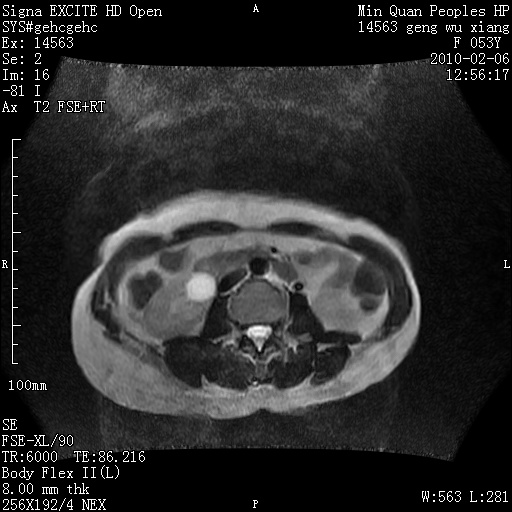

标题: MRI2762:胆道梗阻原因?

f,53y,全身黄染多日。

高位胆道梗阻 胆管癌可能性大

支持 高位胆道梗阻 胆管癌可能性大。